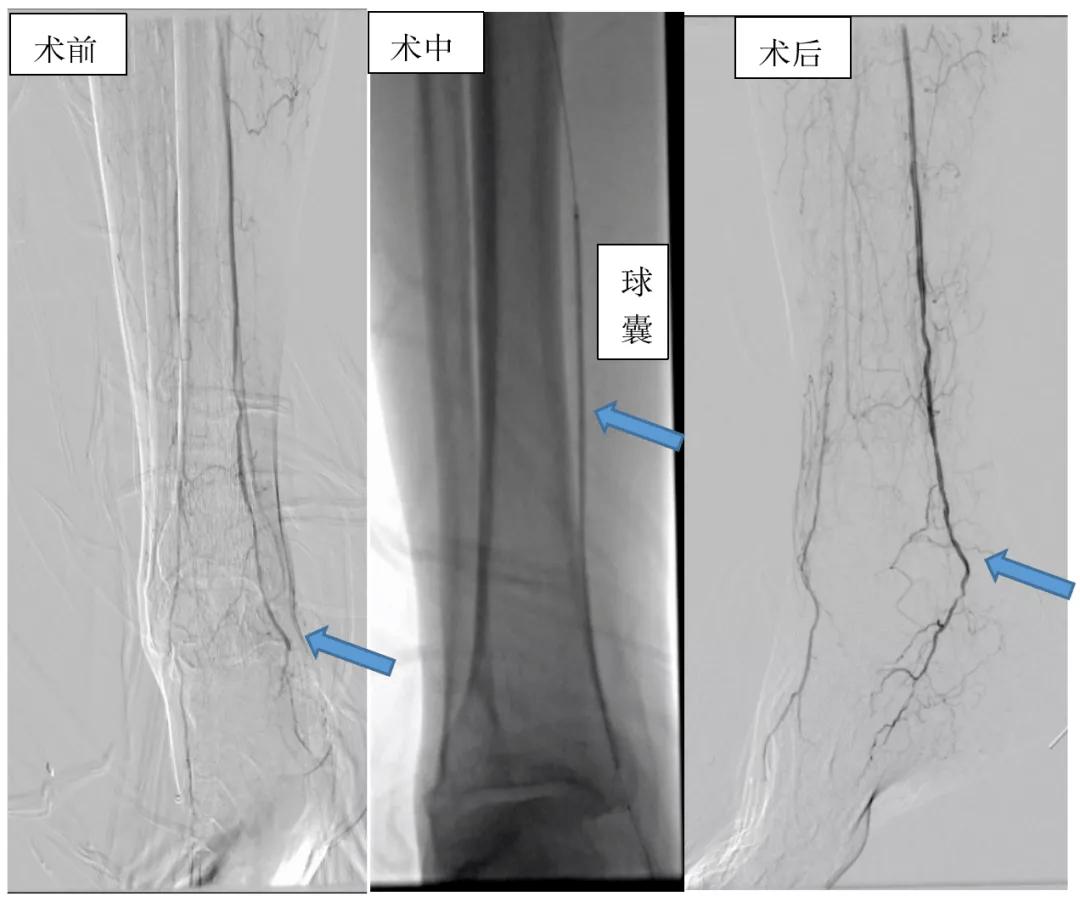

*图示 介入手术开通前右侧腘动脉和胫后动脉多发狭窄闭塞,经过球囊对狭窄段进行分段扩张,术后复查狭窄血管开通良好。